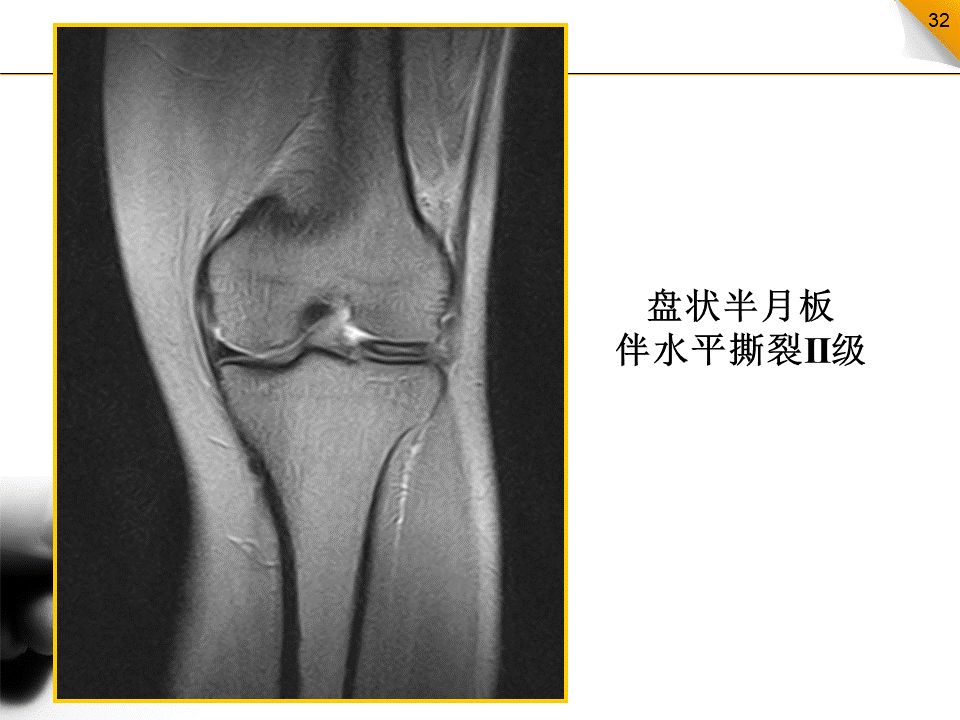

盘状半月板

属发育变异;外侧(占95%)远比内侧多见临床表现为膝部疼痛、弹响和绞锁盘状半月板易发生半月板撕裂和囊肿并可引起软骨磨损或剥脱性骨软骨炎矢状面:连续三个层面均呈双凹镜样表现冠状面:盘状半月板中部宽度显著增宽,与同侧胫骨关节面宽度的比率(板/胫比率)超过50%。板/胫比率:51%-75%--小盘状半月板;大于75%--大盘状半月板